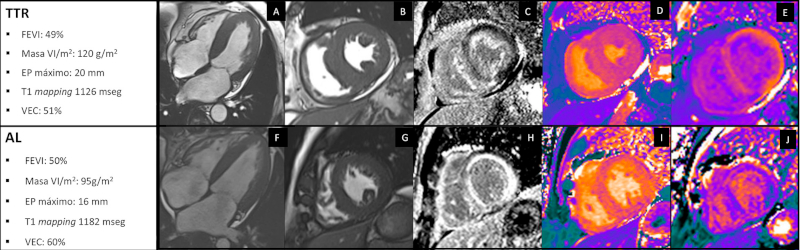

La resonancia magnética cardíaca (RMC) provee una imagen con alta definición para la evaluación estructural, con gran resolución y reproducibilidad, y, adicionalmente, puede realizar caracterización tisular (Figura 2).

Imágenes T1 mapping y volumen de espacio extracelular

Las técnicas de mapeo de T1 o T1 mapping evalúan el tiempo de relajación, píxel por píxel, para caracterizar el miocardio sin contraste. 50 La señal nativa (sin contraste) se prolonga en el miocardio con depósito de material amiloide y es específica para el diagnóstico de AC. 49 Los valores de T1 mapping en equipos de 1,5 tesla (>1060 mseg) permitieron identificar a los pacientes con AC. 48,49,50,51,52,53,54 Sin embargo, valores o puntos de corte diagnósticos de T1 mapping en equipos de 1,5 o 3,0 tesla y diferentes marcas de resonadores requieren mayor estandarización.

Si se mide la relajación del T1, antes y después del gadolinio, se puede estimar el volumen del espacio extracelular (VEC) del miocardio. En condiciones normales, el VEC es menor del 25% de la masa del miocardio. 49 El VEC es una medida estandarizada independiente de la potencia del equipo (p. ej. 1,5 o 3,0 tesla), su marca y dosis de gadolinio administrada. El VEC aumentado se asocia con peor pronóstico en los pacientes con AC y sería un mejor predictor de eventos que el T1 mapping nativo. 50,51,52 Por último, la determinación del VEC, al cuantificar de forma precisa el grado de infiltración amiloide, puede ser de utilidad para evaluar la respuesta al tratamiento. 51